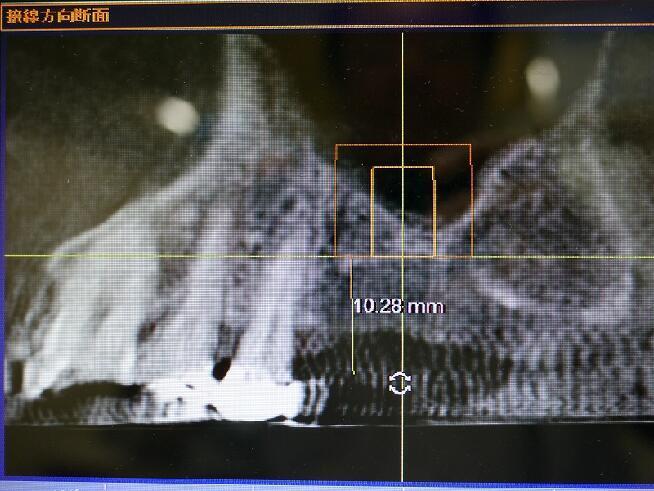

下記の症例では上顎のインプラントを実施するためCT(立体レントゲン)撮影致しました。

その部位の拡大エックス線像です 上顎には他の場所と違い上顎洞という頭を軽くするための空洞があり骨が2~4ミリ程度しかなく、インプラントは大変困難です。

前方から見たエックス線像